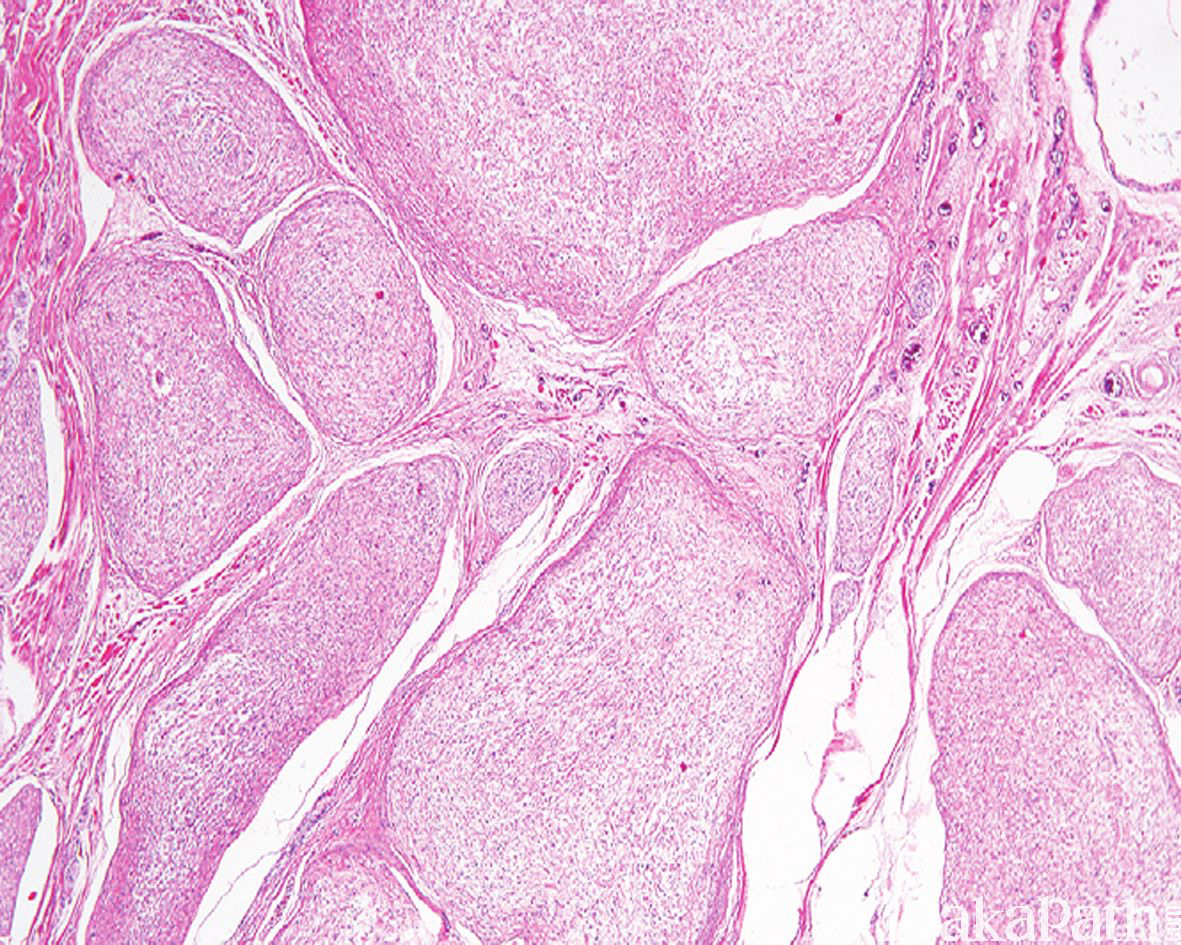

丛状神经纤维瘤

Plexiform Neurofibroma

镜下可见丛状排列的、粗细不一的扭曲、膨大的神经束,丛状结节周围可见神经束膜围绕,结节之间亦可见神经纤维瘤性组织伸入;

瘤细胞梭形,核呈波浪状; 间质疏松,血管较丰富,可伴有明显的黏液样变性;